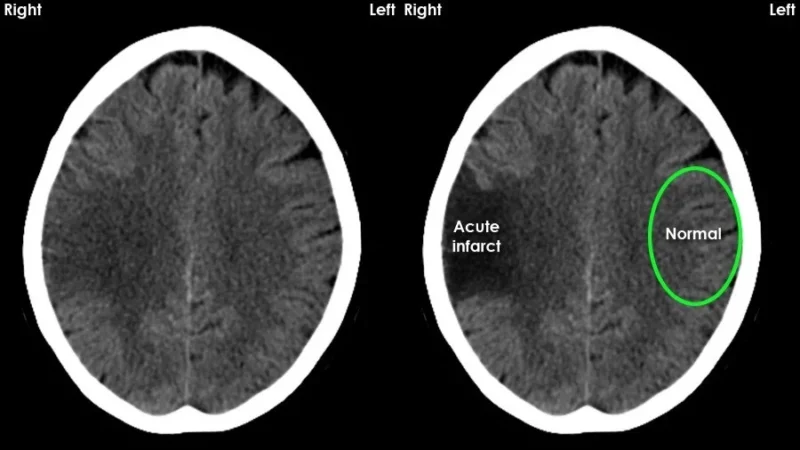

- Ischemic stroke – This is the most common type. A blood clot blocks an artery supplying part of the brain. That blockage prevents oxygen from reaching brain tissue.

Brain cells start dying within minutes. When deprived of oxygen, the affected neurons lose the ability to maintain their electrical balance.

They swell, malfunction, and eventually die. The area directly affected is called the core infarct.